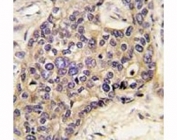

IHC: Formalin-fixed, paraffin-embedded human hepatocellular carcinoma stained with Hepatocyte antibody (SPM582).

Applications Immunohistochemistry (FFPE) : 1-2ug/ml for 30 min at RT